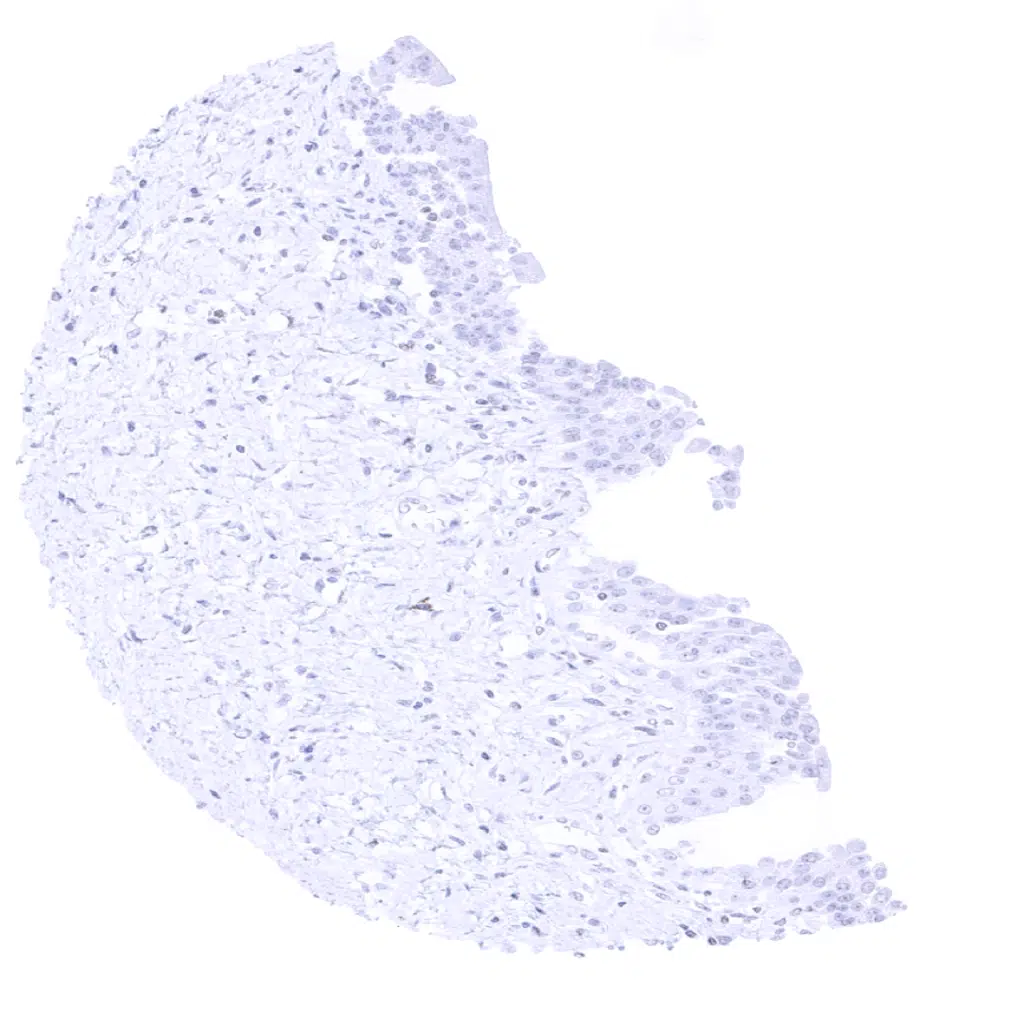

Bronchus, bronchial glands – A weak to moderate GP2 staining occurs in selected cells of bronchial glands. The staining is cytoplasmic but shows a distinct apical predominance.